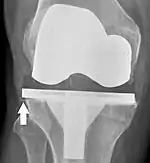

Loosening of the prosthesis can be indicated on X-ray by thin radiolucent spaces around the implant, or more obviously by implant displacement.[54]

Knee replacement is routinely evaluated by X-ray, including the following measures:

- FFC: frontal femoral component angle. It is typically regarded as optimal when being 2–7° in valgus.[61]

- FTC: frontal tibial component angle, which is regarded as optimal when being at a right angle. A varus position of more than 3° has generally been found to increase the failure rate of the prosthesis.[61]

- Anterior femoral notching (the femoral component causing reduced thickness of the distal femur anteriorly), seems to cause an increased risk of fractures when exceeding about 3 mm.[62]

- LTC: lateral (or sagittal) tibial component angle, which is ideally positioned so that the tibia is 0–7° flexed compared to at a right angle with the tibial plate.[61]